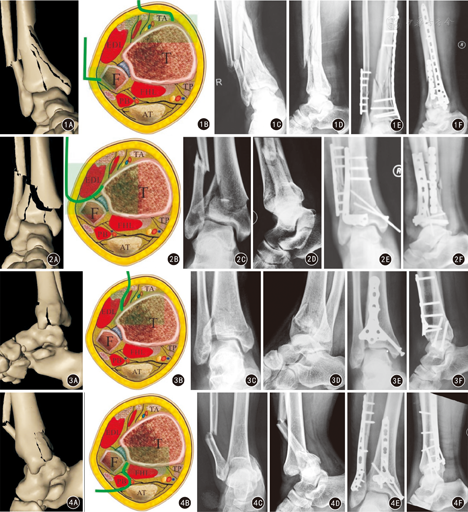

9例因主要压缩骨块位于前内侧取胫骨远端前内侧入路,牵引恢复踝关节力线后直接暴露骨折线及移位骨块,以踝关节面外侧部分为参照标志复位内侧塌陷的关节面骨块,X线透视确认骨折复位良好、关节面平整,将胫骨远端内侧解剖型锁定接骨板作为主要支撑接骨板置于胫骨远端内侧固定骨折。主要骨折线位于踝关节以上、仅有骨折线延续至踝关节的6例采用微创经皮钢板内固定(minimally invasive percutaneous plate osteosynthesis, MIPPO)技术,复位骨折后内踝小切口,胫骨内侧皮下隧道置入胫骨内侧解剖型锁定接骨板支撑固定骨折(图1)。主要移位骨块位于后内侧的3例,取胫骨远端后内侧入路,暴露踝管,以踝管骨面为参照标志复位后内侧塌陷的关节面骨块,于胫骨远端后内侧以T型锁定接骨板为主要支撑接骨板进行支撑固定。

9例因腓骨合并踝关节面前外侧压缩骨折取胫骨远端前外侧入路,直接暴露骨折线,以踝关节面内侧部分为参照标志复位外侧塌陷的关节面骨块。对关节面粉碎较重的骨折,距骨关节面可作为复位的参照,X线透视确认骨折复位良好、关节面平整,将胫骨远端前外侧解剖型锁定接骨板作为主要支撑接骨板置于胫骨远端前外侧,支撑固定骨折(图2)。6例因腓骨合并踝关节面后外侧压缩骨折取后外侧入路,显露后踝,复位后踝骨块后采用1/3管型接骨板、3.5 mm重建接骨板或桡骨远端掌侧接骨板固定。

根据骨折线取胫骨远端前正中入路(9例)或前外侧入路(3例),切口自近端胫前肌腱的内缘至远端距舟关节,切开踝关节囊,直接暴露骨折线,显露踝关节前方及胫骨干骺端的移位骨块;参照胫骨远端前外侧Tilleaux-chaput结节及内后侧,直视下复位,克氏针临时固定;透视确认骨折复位良好、关节面平整,将三叶草形接骨板(图3)或胫骨远端前外侧解剖型锁定接骨板作为主要支撑接骨板置于胫骨前方固定骨折。

根据骨折线及主要骨块位置取胫骨远端后内侧(3例)或后外侧入路(7例),复位塌陷的关节面骨块。X线透视确认骨折复位良好、关节面平整,将1/3管型接骨板或重建接骨板作为主要支撑接骨板置于胫骨远端后内侧或后外侧。见图4。

垂直压缩型Pilon骨折9例均采用前内、后外侧联合入路。根据踝关节水平面CT中的骨折线,参照Tornetta[3]的方法测量骨折角。根据各骨折块的解剖关系和骨折线的走行,选择手术入路和固定方式。(1)骨折角>90°、骨折线呈冠状面走行、压缩骨块偏内侧者,采用前内侧入路联合后外侧入路,通过上述两个切口同时显露胫骨远端的内、前、外、后侧及距骨关节面,将支撑钢板放置在胫骨前内和后外侧垂直骨折线固定骨折。(2)骨折角<90°,骨折线呈矢状面走行等,根据Topliss骨折分型方法[6],标出主要骨折线的位置,把矢状面Pilon骨折分为单纯矢状面劈裂、"T"形和倒"V"形压缩骨块3型。根据骨块及骨折线的位置多采用后外侧入路联合前内侧入路。首先纠正胫骨干骺端短缩畸形,牵引踝关节,通过软组织铰链作用恢复踝关节前、后、前外侧、后外侧和内踝等周围有韧带关节囊附着的骨块。前内侧入路暴露内侧和前外侧骨块间的骨折线,开窗撬拨、暴露中央压缩骨块,以距骨关节面为模板复位压缩的踝关节面并植骨填充骨缺损,克氏针临时固定,关窗,X线透视踝关节机械轴线和关节面复位情况,分别用支撑钢板固定踝关节周围较大骨块(图5)。内固定材料有克氏针、空心钉、解剖型锁定接骨板、T型或1/3管型接骨板、跨关节外固定支架等。